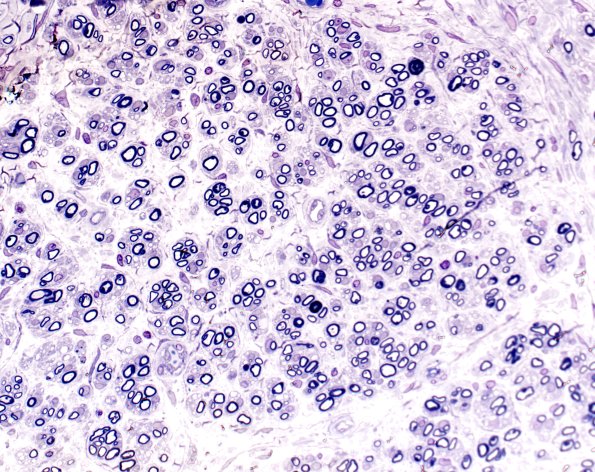

Washington University Experience | PERIPHERAL NEUROPATHY | 19 TRAUMATIC INJURIES | 6H1 Neuroma (Case 6) 20X 2

6H1,2 These two images are from the endoneurium before reaching the point of formation of the mini-fascicles. At this level these structures are regenerative clusters which are significantly smaller than mini-fascicles and are surrounded by Schwann cells rather than perineuria. (Plastic sections)